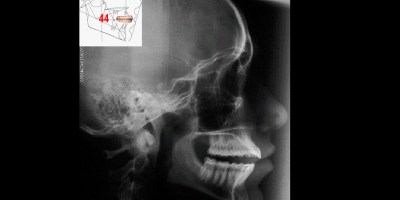

Osteonecrose da Cabeça da Mandíbula: recuperação da alteração da medular óssea.

Recaptura do Disco Articular: paciente com significativa assimetria das cabeças mandibulares e deslocamento redutível unilateral. Caso clínico

Tratamento das Patologias da ATM: primeira e segunda fase (ortodontia tridimensional) em uma paciente hiperlassa com hipossinal na medular da cabeça da mandíbula. Caso clínico.